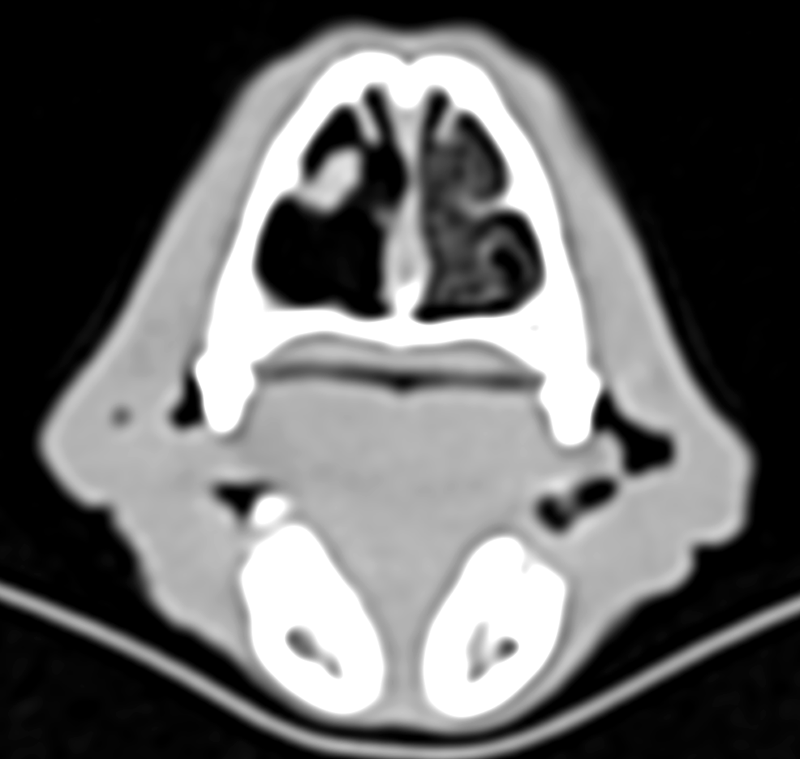

La cirugía termina cando se ha eliminado la masa por completo, además de los márgenes de seguridad que hayamos establecido, si nuestra intención es curativa o cuando consigamos disminuir si tamaño a aquel que elimine los sintomas y mejore la calidad de vida del animal si nuestro planteamiento terapeutico es paliativo. Las imágenes muestran una tomografía posoperatoria del mismo punto anatómico una vez eliminado el tumor.